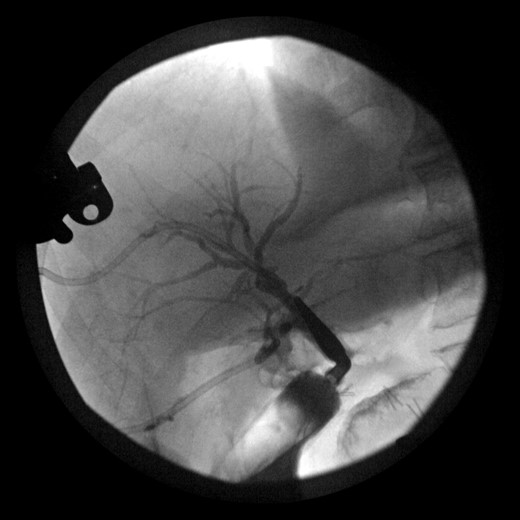

During this operation, the porta was dissected and the common and proper hepatic arteries were identified and preserved. We were unable to palpate the previously placed percutaneous biliary catheters due to the high placement above the hilum at the level of multiple clips. We transected the CBD distally and removed numerous clips, finally noting bile drainage, but were unable to identify a cholangiogram catheter. We then identified a second tubular structure more lateral to the duct. We elected to transect this tissue, identifying a second extrahepatic bile duct. The anterior percutaneous catheter was identified proximally within the duct. An on-table cholangiogram with fluoroscopy was performed noting two separate extrahepatic biliary systems, draining the right and left lobes of the liver, respectively (Figs 3 and 4). Both distal ducts were ligated to definitively close the orifice to the duodenum and prevent spillage. A Roux limb of jejunum was created and anastomosed in a retrocolic fashion to the two separate hepatic ducts at the level of the hilum. A drain was placed, and there was no evidence of bile leakage.

Intraoperative cholangiogram of the right ductal system through the extrahepatic right CBD.